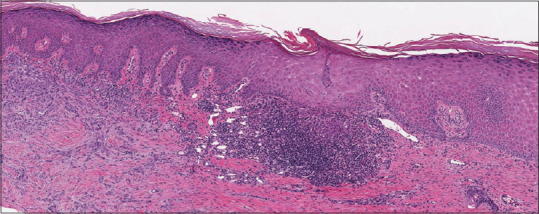

Basal cell carcinoma (BCC) is the most common form of skin cancer, which presents with local invasion, has low metastasizing potential and a cure rate of 100% after surgical excision. BCC commonly involves sun-exposed areas with approximately 80%-85% of BCC located on the head or neck, 15% on the trunk, and <2% in unusual areas such as the abdomen, genitals, perianal skin, lateral edge of the foot, axilla, superior or inferior lip.